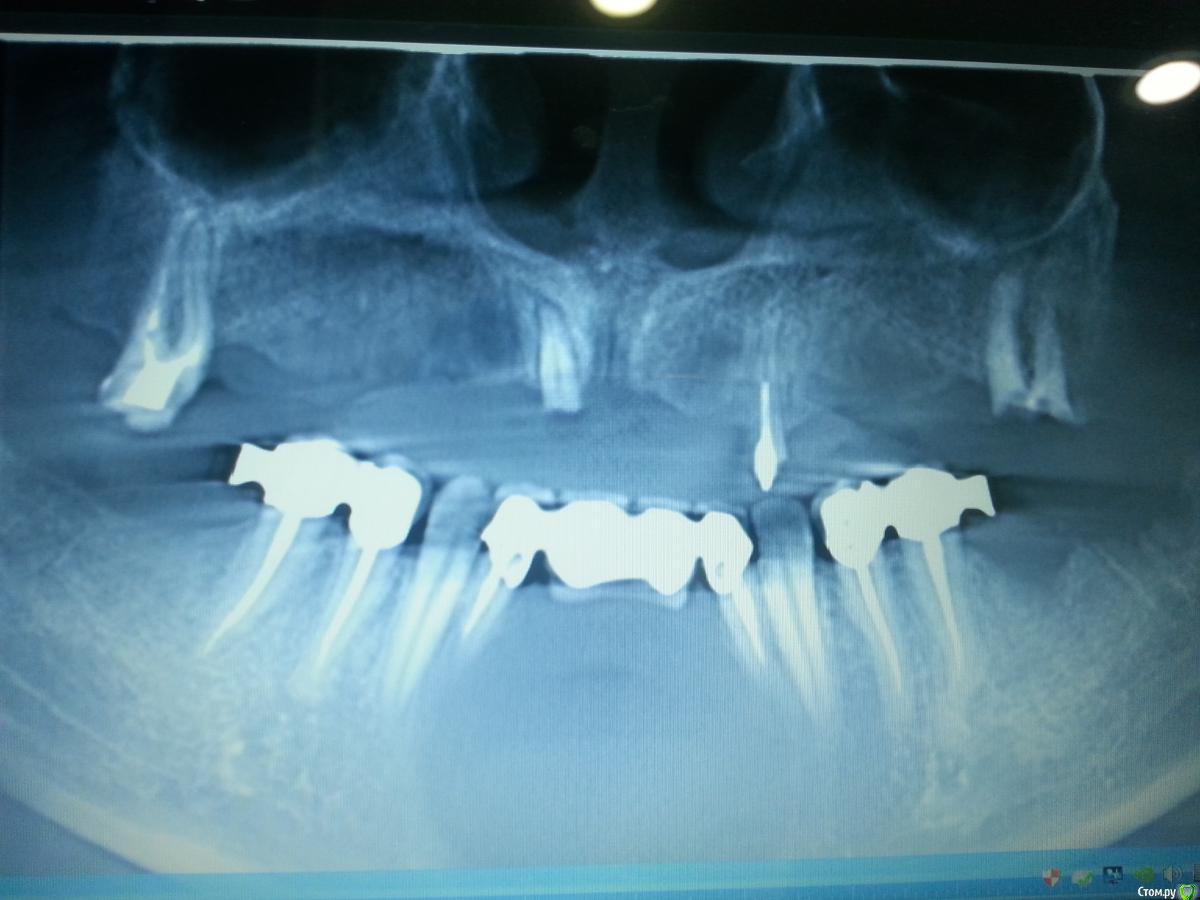

uzstom Опубликовано 29 мая, 2015 Поделиться Опубликовано 29 мая, 2015 Добрый день коллеги. Пациентка 29 лет. Хочет несъемную конструкцию на верхней челюсти. Нужен совет по костной пластике. Как нарастить? Спасибо. http://images.vfl.ru/ii/1432877759/d9165bd6/8879105_m.jpg http://images.vfl.ru/ii/1432877759/ef205713/8879106_m.jpg http://images.vfl.ru/ii/1432877760/acc2a5c3/8879107_m.jpg http://images.vfl.ru/ii/1432877761/6338400e/8879108_m.jpg Ссылка на комментарий

zzkz Опубликовано 29 мая, 2015 Поделиться Опубликовано 29 мая, 2015 29 лет? Удалить все зубы на в.ч. и НКР + с небной стороны, все на 6 после этогоНо тут что то не так. Как в таком возрасте и с такими зубами И не видится ли вам на н.ч. во фронте обширная деструкция? По этому снимку сложно понять 1 Ссылка на комментарий

uzstom Опубликовано 29 мая, 2015 Автор Поделиться Опубликовано 29 мая, 2015 29 лет? Удалить все зубы на в.ч. и НКР + с небной стороны, все на 6 после этогоНо тут что то не так. Как в таком возрасте и с такими зубами И не видится ли вам на н.ч. во фронте обширная деструкция? По этому снимку сложно понятьСпасибо за ответ. На нижней челюсти деструкции нет. Панорама из кт по этому такая картинка. Сам думаю про нкр с титановой сеткой. Фронт, слева и справа отдельно сеткой нарастить. Таких работ еще не было в моей практике. Жду совета опытных коллег. Ссылка на комментарий

faity Опубликовано 29 мая, 2015 Поделиться Опубликовано 29 мая, 2015 На нижней челюсти деструкции нет. Панорама из кт по этому такая картинка. а можно срезы? слишком подозрительно располагаются зубы Ссылка на комментарий